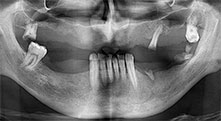

Bratu: We routinely use the instruments for harvesting bone blocks and splitting alveolar ridges. We also use the Piezomed B6/B7 for osteotomy of impacted teeth and removing failed implants. All indications that require deep, clean cuts.

Bratu: We prefer to harvest bone from the external oblique ridge of the posterior mandible, not from the interforaminal region. After the soft-tissue incision, we use the new saws to define the amount of bone to harvest. With this approach, we also use them for the entire preparation in almost 80% of cases. We may also use other piezo instruments and then at the end a chisel to mobilize the block. We find that this is a very effective surgical technique.

Bratu: We like to use the sandwich technique for augmentation in the lateral mandible. A bone cover is prepared with the piezo saw and the crestal fragment is fixed with microscrews. We place a mixture of autologous bone and xenogenic bone replacement material in between. This works very reliably. You should always ensure sufficiently dimensioned vertical cuts when splitting the alveolar ridge in the mandible. Otherwise the bone may fracture easily.